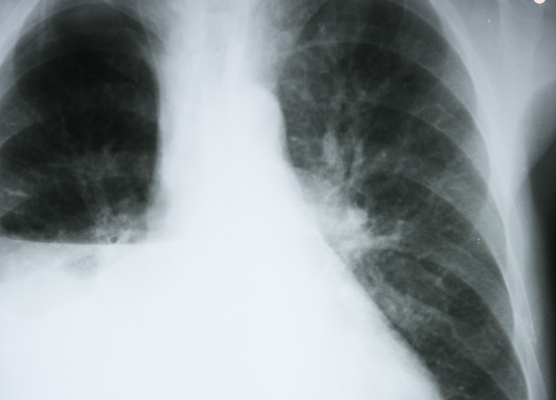

raiox

Abordagem fisioterapêutica no derrame pleural parapneumônico.

14 de agosto de 2015 Marketing Fisioteraloucos 0 comentários derrame parapneumônico, derrame pleural, fisioterapia, fisioterapia no derrame pleural, fisioterapia respiratória

O derrame pleural parapneumônico (DPP) ocorre durante o curso clínico de uma pneumonia ou abscesso pulmonar. Sua incidência é freqüentemente